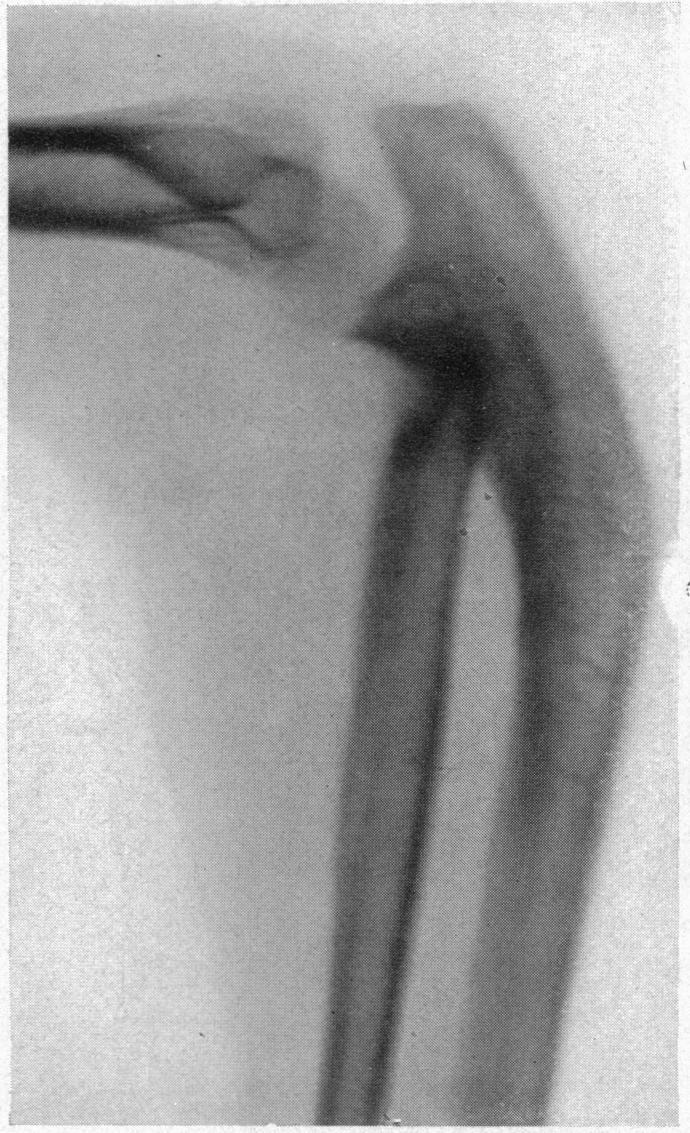

FRACTURES OF THE HEAD AND NECK OF THE RADIUS.

Ann Surg. 1926 Feb;83(2):267-78. doi: 10.1097/00000658-192602000-00015.